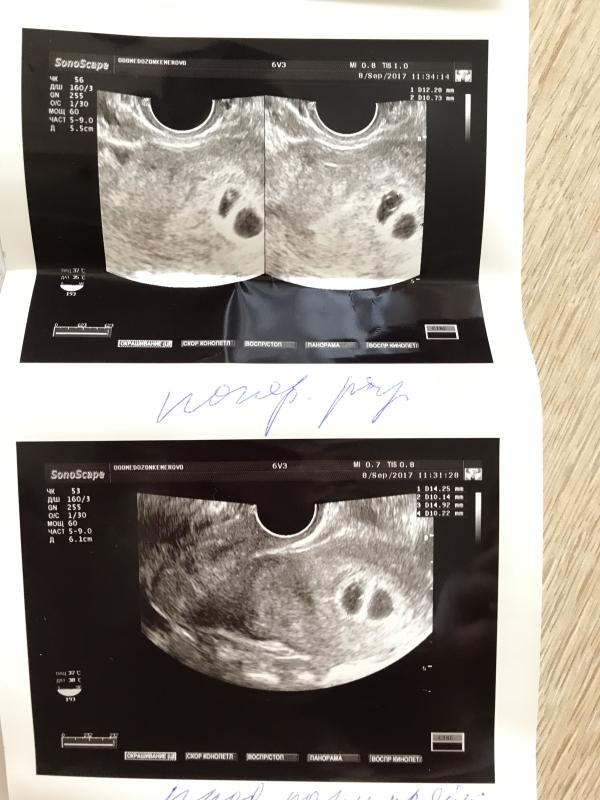

Сегодня было первое УЗИ. Когда врач, глядя на экран,сказала "О,Боже...долечились" я испытала гамму эмоций 😱😨😐😏😝😂 Два плодных яйца!!! Два! Это у меня где в роду ни у мужа ни у меня нет двойняшек вообще. На меня просто истерический смех напал😂 Но при рассмотрении оказалась что эмбриончик только один, что немного расстроило (я уже успела размечтаться). Мой малыш всего 3,6мм,но у него уже чётко прослеживается сердцебиение ❤️ сегодня мужа буду пугать снимком с двумя плодными яйцами,посмотреть хочу на ...